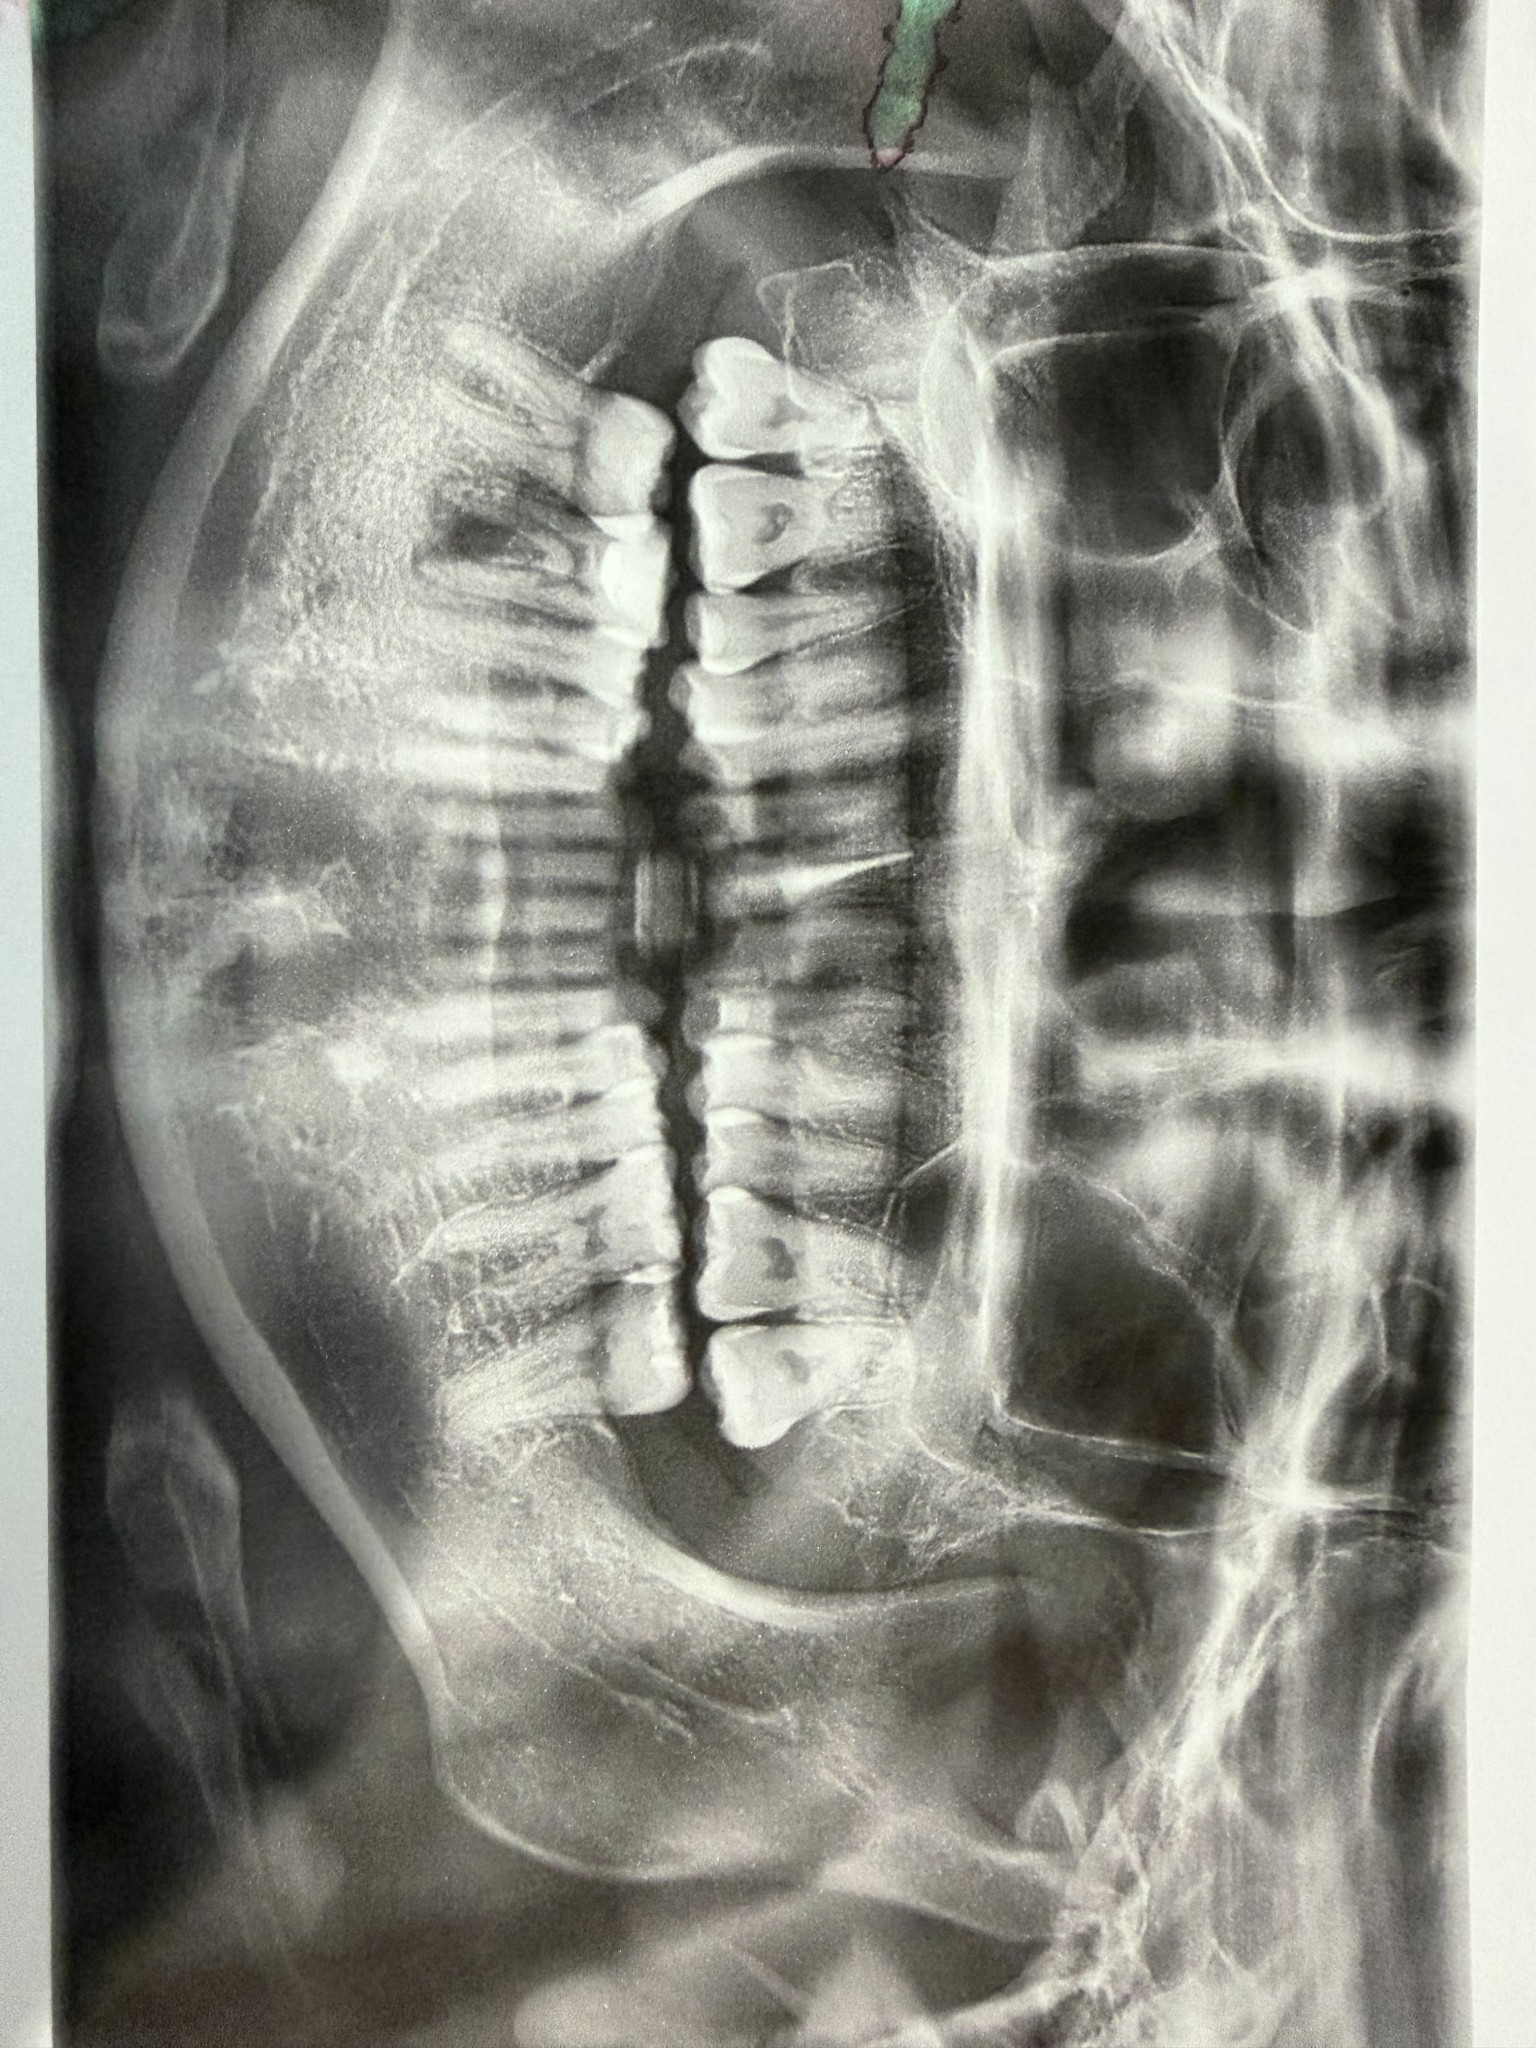

ขอสอบถามค่ะ พอดีเรามีปัญหารากฟัน ฟันล่างยื่นออกมา และอื่นๆตามภาพฟิล์มเลยค่ะ เคยไปสอบถามคลินิค เขาบอกว่าเป็นงานยากส่วนใหญ่ไม่รับเลย ให้ไปที่โรงพยาบาล เราไม่ทราบรายละเอียดเลย ปกติโรงพยาบาลจัดฟันได้ด้วยหรอคะ แล้วปกติส่วนมากจะไปที่โรงพยาบาลไหนกัน สอบถามผู้รุ้หน่อยค่ะ